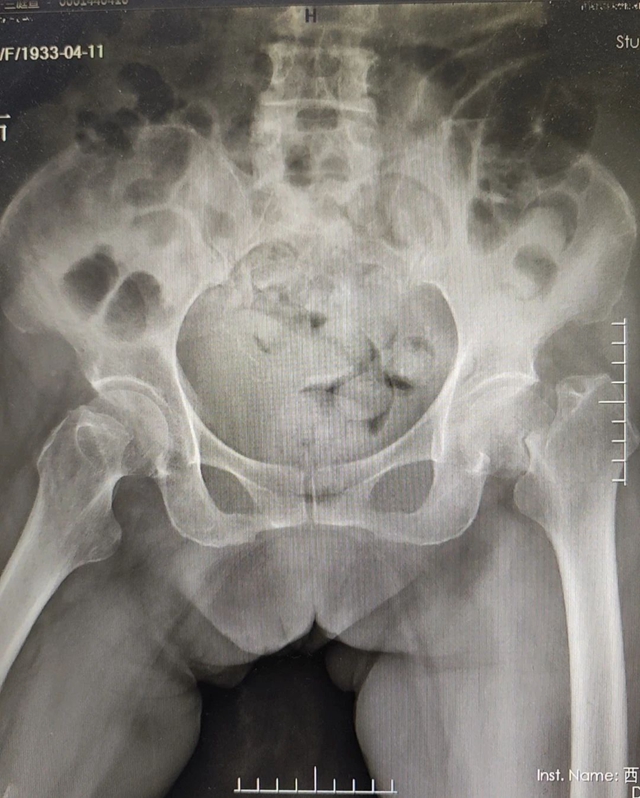

前段时间,年过九旬的兰婆婆却不小心在家中摔倒,在送往医院后,兰婆婆被诊断为股骨颈骨折。

这种骨折是老年患者最常见的骨折之一,被称为“人生最后一次骨折”,特别是80岁以上的高龄老人如果发生这种骨折,即使经过保守治疗,死亡率仍然高达30%以上。

兰婆婆由于患有高血压、心脏病、糖尿病等多种基础疾病,导致自身身体状况欠佳。对于这样的高龄老人来说,手术麻醉风险极高,但若不进行手术治疗,她又面临着长期卧床、并发症缠身、最终危及生命的困境。

骨与关节外科医生们详细询问了她的病史,并进行了全面的检查,结果显示兰婆婆患有冠心病而需口服抗凝药物,其血糖水平持续高于20mmol/L,同时心电图也呈现出异常状态,这些情况都为治疗带来了额外的挑战。

骨与关节外科主任李忠在详细查房后认为,尽管面临重重困难,但尽早进行手术仍是必要的。在心血管内科和内分泌与代谢内科的专家指导下,兰婆婆心律失常和高血糖的状况得到了有效改善。基于此,骨与关节外科副主任尹一然与白毅平讨论后,为兰婆婆精心策划了喉罩全麻复合神经阻滞下的人工半髋关节置换手术方案。经过周密的术前评估和细致的准备,手术顺利进行。